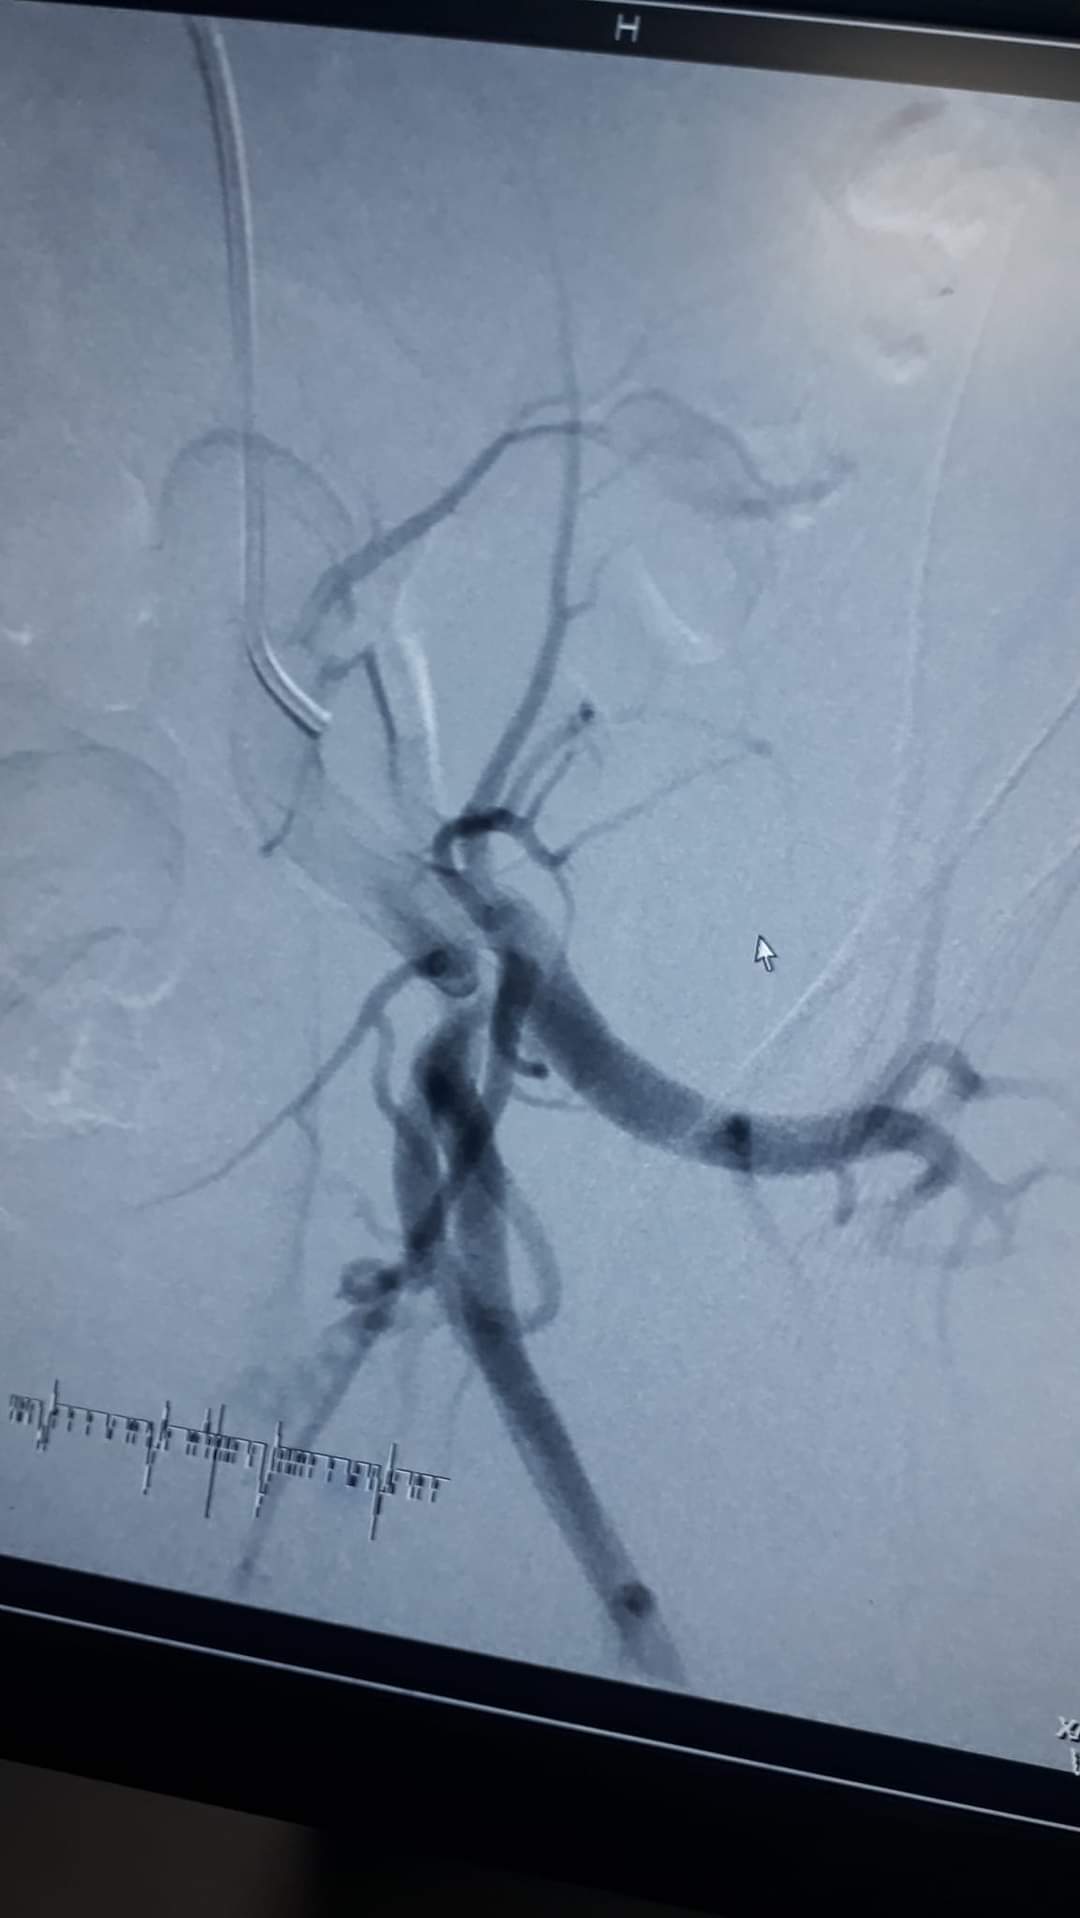

تمكن طاقم طبي فلسطيني من قطاع غزة من انقاذ حياة شاب في العشرين من عمره، بعد إجراء عملية جراحية، وُصفت "بالنادرة".

حيث تم إغلاق إنتفاخ في أحد الشرايين المتفرعة من "الشريان الحرقفي العميق" في الحوض. حيث كان يتسبب في ألام شديدة لمريض في الثانية والعشرين من عمره.

وقال الدكتور محمد كلوب استشاري اول جراحة الأوعية الدموية والقسطرة الطرفية، أن حياة المريض كانت محفوفة بالخطر الشديد، نتيجة الوصلات الشريانية والوريدية التي كانت معرضة للإنفجار وتهدد حياة المريض.

واعتبر الدكتور كلوب في تصريح صحفي أن هذه من الحالات النادرة جداً، وقد أُجريت هذه العملية، برئاسة دكتور محمد مطر.